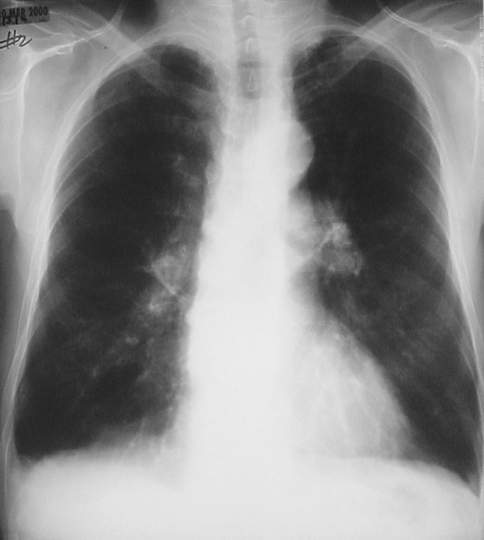

Image 3.1

The chest radiograph in posterior-anterior view above and lateral view below demonstrates a marked increase in size of the chest cavity. Note the increased lucency due to the loss of lung parenchyma. There is prominence of the pulmonary arteries at the hila, indicative of pulmonary hypertension. |